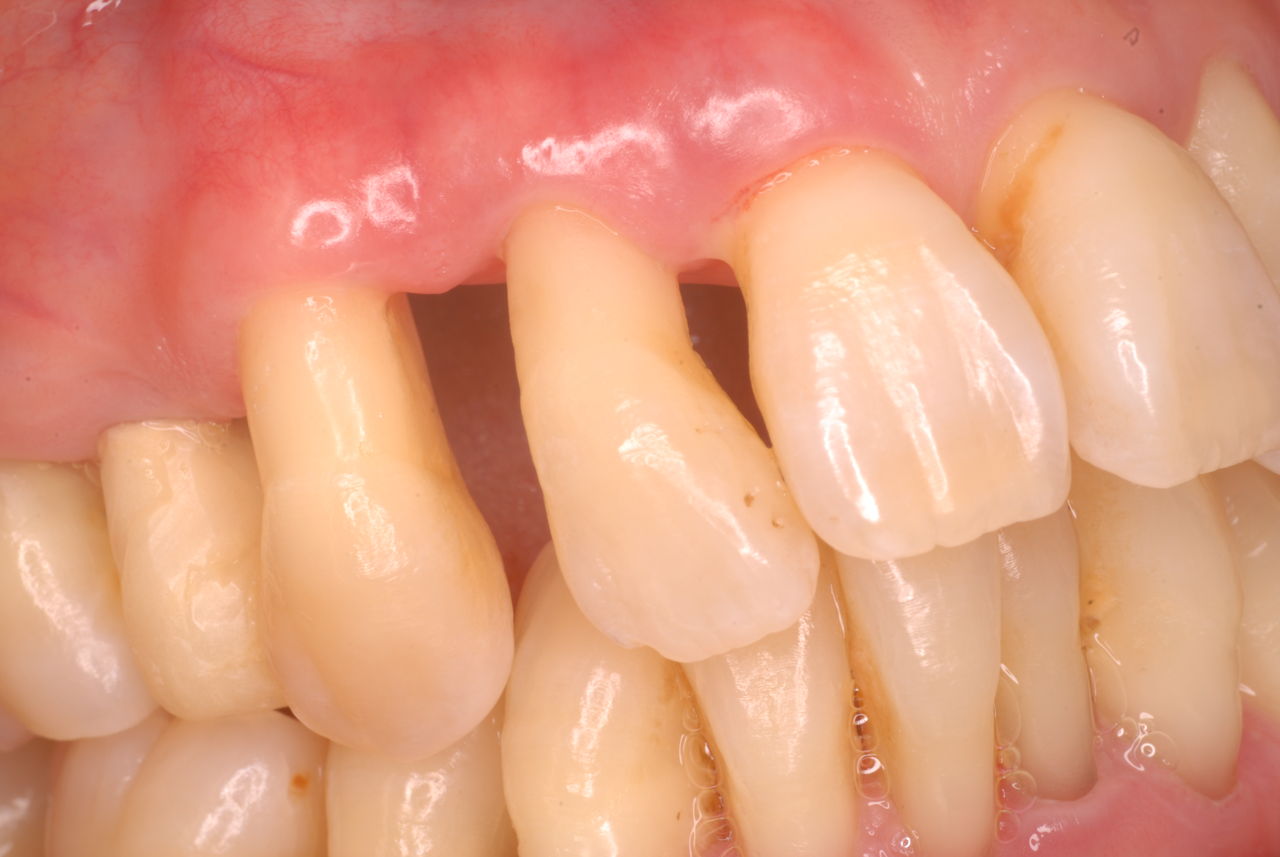

¤½¤ÎÃæ¤Ç¤â°ìÈÖ¶ìÏ«¤·¤¿¤Î¤Ï¡¢ÉôʬŪÆþ¤ì»õ¤äÁíÆþ¤ì»õ¤Ç¤·¤¿¡£¤¤¤Þ¤À¤ËǺ¤à»ö¤â¤¢¤ë¤°¤é¤¤¤Ç¤¹¡£

¹«¤Ë¤Ï¡¢¿³ÈþŪÆþ¤ì»õ¤ä¤¬¤Á¤Ã¤È¤·¤ÆÆ°¤«¤Ê¤¤Æþ¤ì»õ¤ÎÀëÅÁ¡¢¤¹¤Ê¤ï¤ÁÁªÂò»è¤òÍ¿¤¨¤ë¹¹ðÀëÅÁ¤ò¤µ¤ì¤Æ¤¤¤ë»õ²Ê°å±¡¤ò»¶¸«¤¤¤¿¤·¤Þ¤¹¡£

¤·¤«¤·¡¢³ØÌäŪ²Ê³ØÀ¤ò̵»ë¤·¤¿Æþ¤ì»õ¤Ï³ú¤á¤Ê¤¤¤É¤³¤í¤«»Ä¸¤·¤Æ¤¤¤ë»õ¤ò°ú¤È´¤¤¤¿¤ê¡¢Ç˲õ¤¹¤ë¶§´ï¤È¤Ê¤ë¤Î¤Ç¤¹¡£

ÁíµÁ»õ¤Ç¤Ï¹Å¤¤»õ·Ô¤òÇ˲õ¤·¤Æ¹ü¤ò¤È¤«¤·¡¢Æþ¤ì»õ¤½¤Îʪ¤òÆþ¤ì¤é¤ì¤Ê¤¤¤Û¤É¤Î¹üÇ˲õ¤òÍ褷¤Æ¤·¤Þ¤¦Êý¤â¤¤¤ë¤Î¤Ç¤¹¡£

°åÎŹ԰٤ǤϤ¢¤ê¤Þ¤»¤ó¤¬¡¢²Ê³ØÅª»×¹Í¤ÇºîÀ®¤·¤Ê¤¤¤ÈÄˤ¯¤ÆÆþ¤ì¤é¤ì¤Ê¤¤¤·¡¢»Ä¸»õ²ç¤âÇ˲õ¤µ¤ì¡¢»Ä¸¤·¤Æ¤¤¤ë³Ü¤Î¹ü¤âÇ˲õ¤µ¤ì¤Æ¤¤¤¯¤Î¤Ç¤¹¡£

¸½ºß¤Ç¤â¿¿ô¤ÎÊý¤¬Æþ¤ì»õ¤Ç³ú¤á¤Ê¤¤¤È¤«»Ä¤ê¤Î»õ¤¬¥À¥á¤Ë¤Ê¤ë»ö¤Ç¤À¤ó¤À¤ó»õ¤ò¼º¤¤¶ìÏ«¤µ¤ì¤ëÊý¤¬Â¿¤¤¤Î¤Ç¤¹¡£

¤«¤è¤¦¤Ê²Ê³ØÅª»×¹Í¤ÇºîÀ®¤µ¤ì¤¿¡ÊËÜÅö¤Ë¶µ²Ê½ñŪ¡ËÆþ¤ì»õ¤Ï²¿Ç¯·Ð¤Ã¤Æ¤âÊѲ½¤·¤Þ¤»¤ó¤·¡¢»õ·Ô¤Î²¼¤Î¹ü¤ÎÇ˲õ¤Ï¤¹¤¯¤Ê¤¤¤Ç¤¹¤·¡¢°ìÀ¸½¤Íý¤·¤Ê¤¬¤é»È¤¨¤ë¤â¤Î¤Ê¤Î¤Ç¤¹¡£